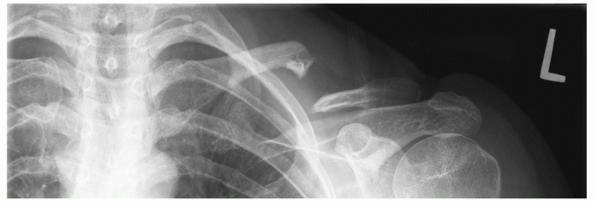

FIGURE 36-6

Anteroposterior radiograph of the clavicle in a 42-year-old man involved in a motor-vehicle collision. Associated injuries include multiple ipsilateral upper rib fractures, an ipsilateral pneumothorax (arrows outlining collapsed lung), and multiple lower extremity fractures. This patient has four relative indications for operative fixation: (i) the severe displacement of the clavicle fracture, (ii) the multiple upper rib fractures, which tend to destabilize the shoulder girdle, (iii) the associated lower extremity fractures and the resultant need for immediate upper extremity use, and (iv) the pneumothorax, which is indicative of the degree of trauma applied to the shoulder.  |